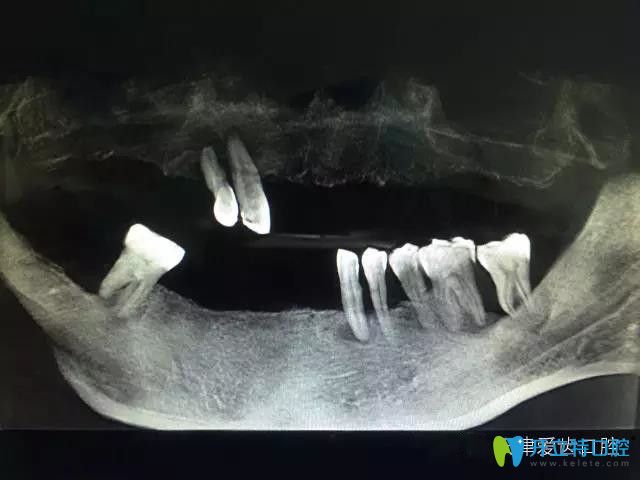

顧客女兒稱,老父親是一位80歲曾三次經(jīng)歷腸癌、胃癌困擾的老先生,自己經(jīng)過對天津牙科排名了解后,帶父親來到了愛齒口腔找郭平川醫(yī)生做半口牙種植,希望能夠補(bǔ)齊自己缺失的牙齒,讓生活更有質(zhì)量。經(jīng)過多方檢查和商議決定采用數(shù)字化種植導(dǎo)板技術(shù)為老人進(jìn)行種植牙。經(jīng)過短期的恢復(fù),老人很快就能夠正常飲食,生活得很舒心。為了感謝郭院長還特意送來了錦旗。